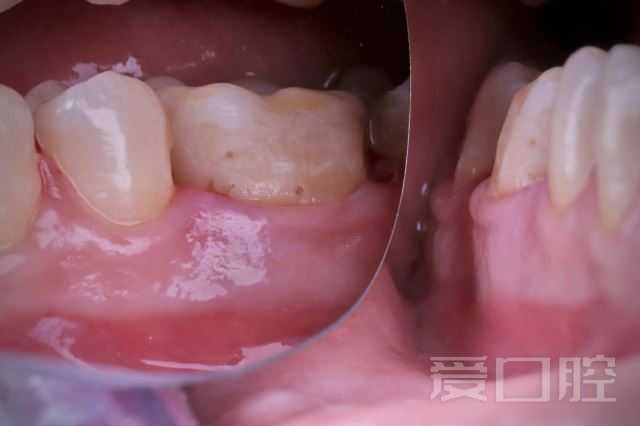

[病例] 下颌第一磨牙嵌体修复1例

下颌第一磨牙嵌体修复1例

by Dr.Ismail Hamada